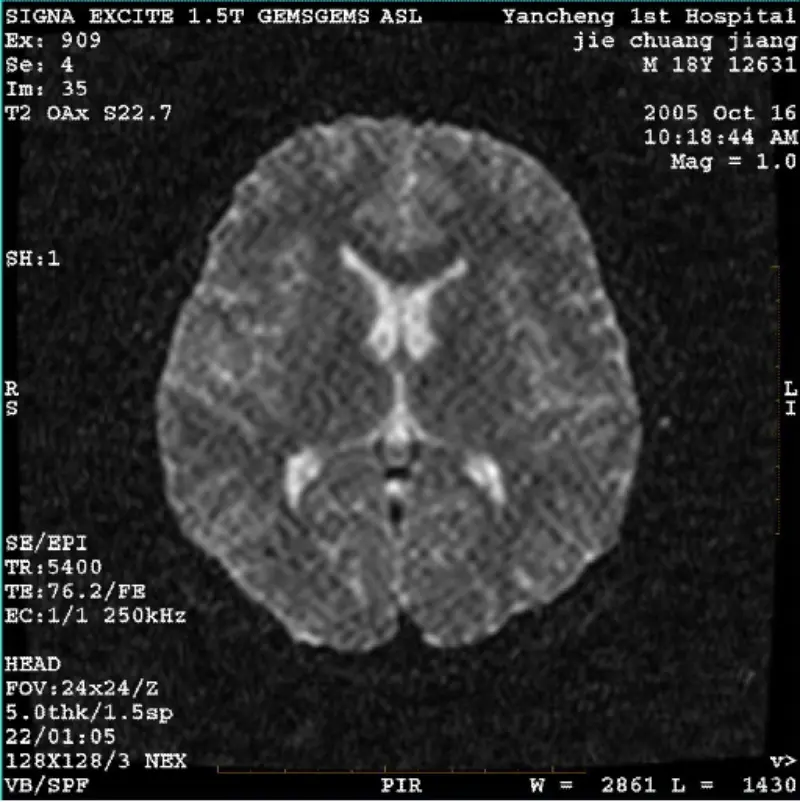

மேலும் படிக்கசிஸ்டம்: 1.5டி சிக்னா ட்வின் எக்ஸைட் II (மென்பொருள் பதிப்பு 11.0எம்4) பிரச்சனை/அறிகுறி DWI (ஜூம் பயன்முறை மற்றும் முழுப் பயன்முறை) மற்றும் ஃபீஸ்டா (ஜூம் பயன்முறை மற்றும் முழுப் பயன்முறை) படம் உள்ளது உடல் சுருள் அல்லது தலையைப் பயன்படுத்தும் போது கண்ணுக்குத் தெரியும் ரெட்டிகுலேட் அல்லது கார்டுராய......